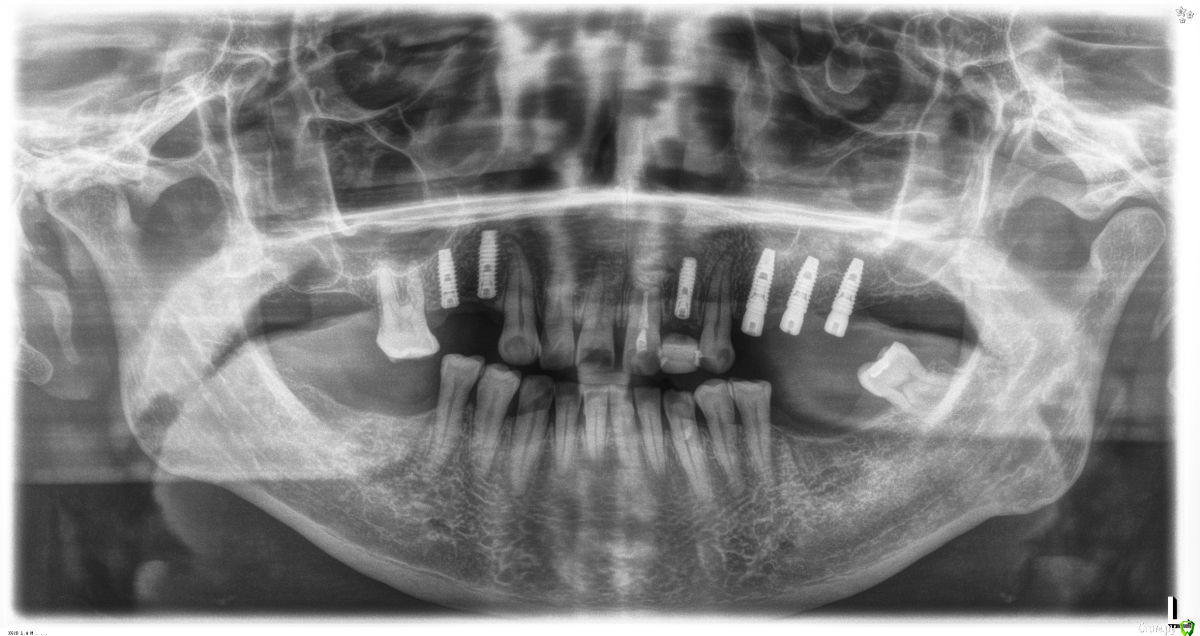

Fibez Опубликовано 8 апреля, 2016 Поделиться Опубликовано 8 апреля, 2016 Наклон мешает протезированию тем, что иногда трансфер упирается в зуб. Что бесит ортопеда. Плюс не нужная нагрузка на фиксирующие винты. Ссылка на комментарий

diesel87 Опубликовано 8 апреля, 2016 Поделиться Опубликовано 8 апреля, 2016 22 одномоментно ставили? Почему заглушили, а не формик поставили сразу? Ссылка на комментарий

Robinbobin Опубликовано 8 апреля, 2016 Автор Поделиться Опубликовано 8 апреля, 2016 22 одномоментно ставили? Почему заглушили, а не формик поставили сразу?22 одномоментно все верно. Ортопед попросил заглушить))) формики ему не нравятся Ссылка на комментарий

diesel87 Опубликовано 8 апреля, 2016 Поделиться Опубликовано 8 апреля, 2016 22 одномоментно все верно. Ортопед попросил заглушить))) формики ему не нравятся А зря, сразу сст и графт костной, фдм или временная коронка лучшая поддержка всего этого. И формирователь поставили вровень или на мм выше уровня десны и никому бы он не мешал. Ссылка на комментарий